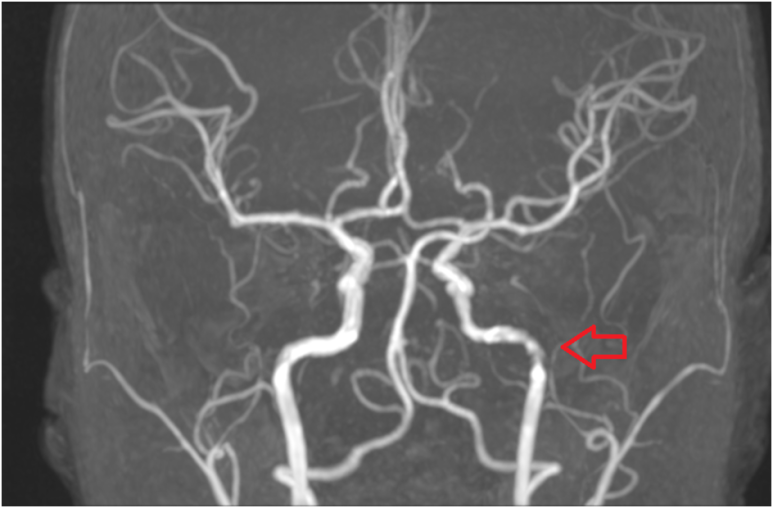

뇌 MRA에서 좌측 뇌혈관 협착이 확인되어 증상과 일치했습니다. 환자분은 추가적인 치료 및 수술적 조치가 필요한 상황으로 상급병원에 전원하였습니다.

MRA: 좌측 혈관 협착 확인 → 상급병원 전원(치료/수술 평가).

• MRA: 좌측 협착 MRA: 좌측 협착